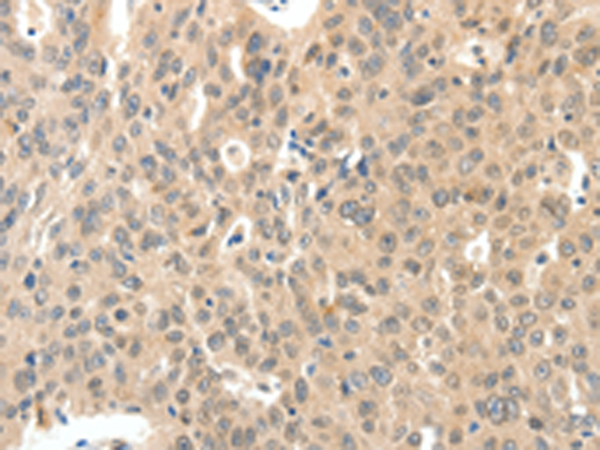

分类: 科研抗体货号: P04438别名: ROS; MCF3; c-ros-1应用: IHC反应种属: Human